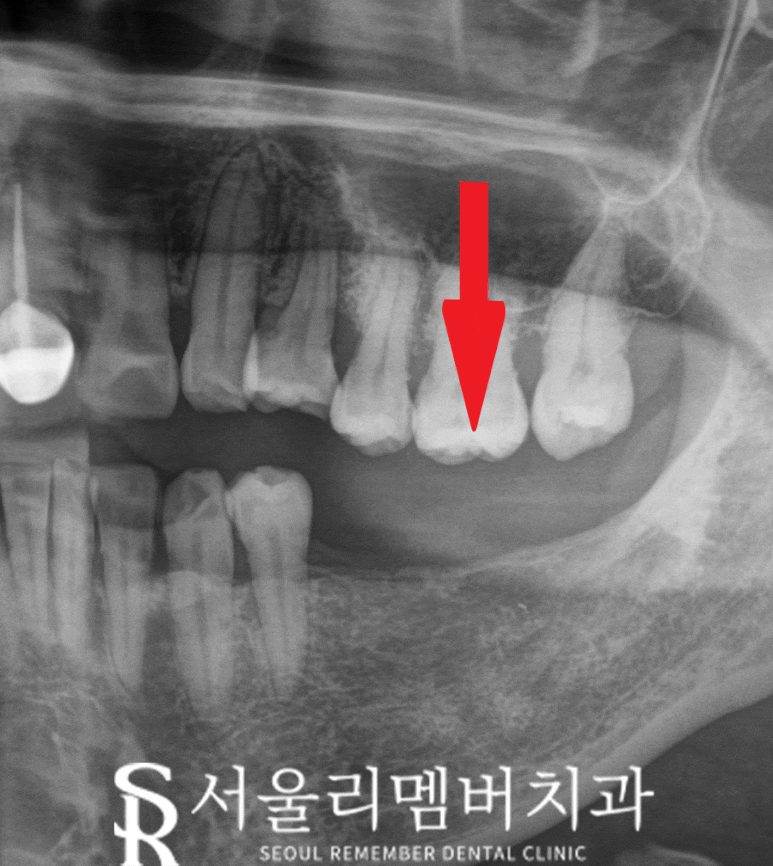

엑스레이로 사진을 찍어 확인해 보니

전체적으로 치조골 퇴축되어 있고

특히 10번 대 보철 치료한 곳은

더 심하게 뼈가 내려가 있어

핀셋으로 살짝 흔들어보아도

동요가 느껴질 정도로 흔들림이

크게 느껴졌습니다.

오래된 보철과 잇몸 사이의

공간이 만들어지면서 식편압입이 생기고

이에 따라 치주염이 발생하면서

흔들리기 시작한거라고 판단합니다.